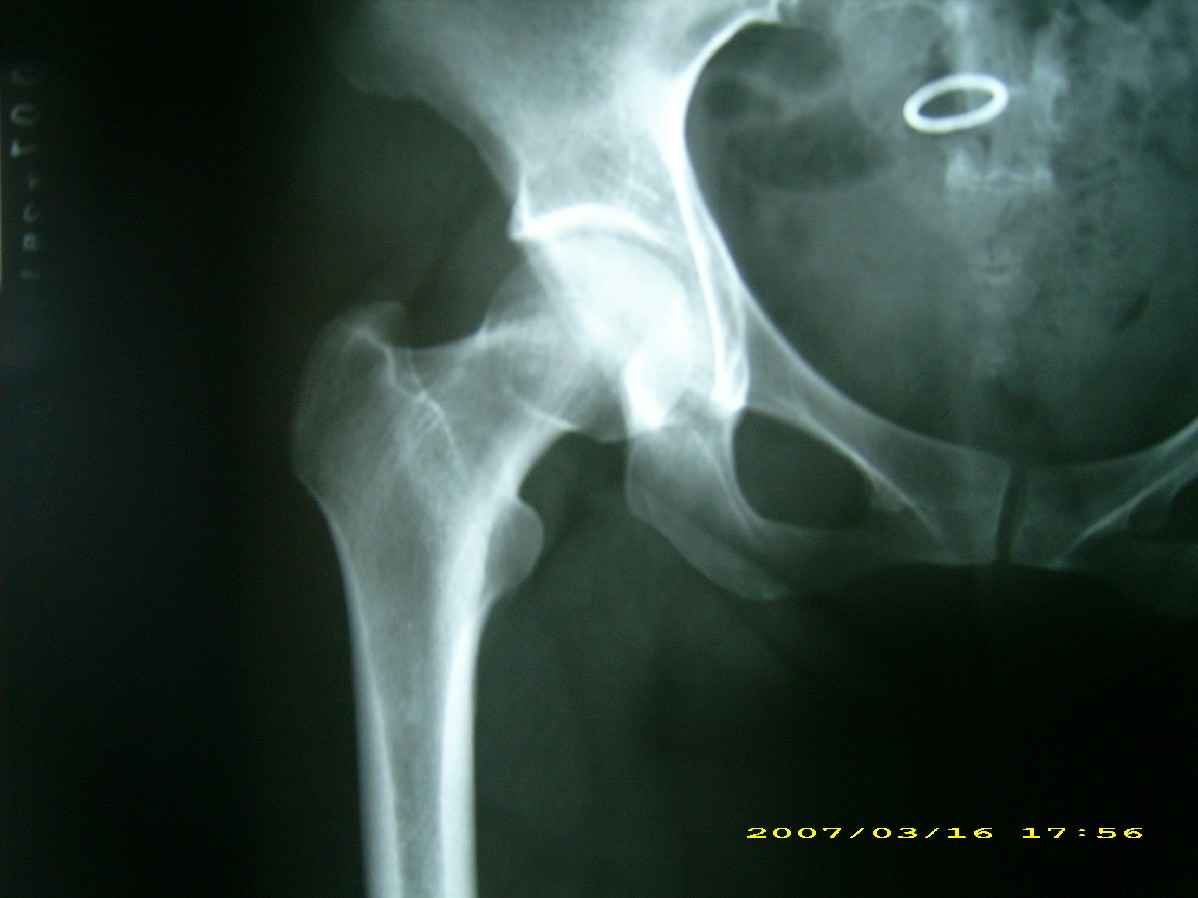

患者,女,因外伤就诊。摄骨盆及右股骨。当时报告骨盆未见明显异常,右股骨中段粉碎性骨折。五天后行股骨中段骨折内固定手术,术中摄床边片示股骨颈骨折。现把术前和术中图像上传。请大家高诊,分析股骨颈骨折是术前漏诊还是其他原因。术前骨盆片右股骨颈显示欠佳是由于股骨中段骨折无法将股骨颈完全显示。

术前片示右股骨颈未见明显骨折征象。如果事先有骨折,由于投照位置原因,骨折线也是完全有可能被挡住重叠而看不见的(并且本例骨折对位良好,更有可能看不到)。所以要凭此判断述前是否有骨折不容易

术前由于位置原因使股骨颈未全部显示,骨折线与股骨头重叠,骨折也可以使股骨颈缩短

回头看术前片,可见一低密透光区.

关于楼主说的骨折线的形态,的确和一般外伤的有种不太一样的感觉,上方裂隙较明显,下方骨皮质“连续”,我认为成年人应该是全部断了的,不全骨折的可能性非常非常小,该片恰好无法全部显示骨折线。骨折线的形态不能判定术前还是术后骨折。以上只是个人小小看法,请各位老师指正为谢!